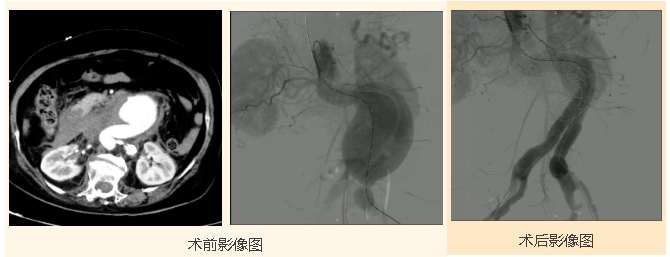

86岁的王大爷(化名)9厘米大的巨大腹主动脉瘤濒临破裂、腹主动脉扭曲严重,且瘤颈较短,血管条件不佳,还合并冠心病、肺气肿病史,麻醉风险极高、手术难度大。

郭平凡教授团队大胆创新,在局麻下实施“腹主动脉覆膜支架腔内隔绝术”,仅通过微小创口精准隔绝瘤体,成功规避麻醉风险。术后王大爷恢复良好。